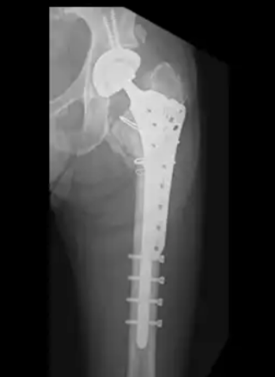

軟骨がほとんど残らない重度の変形では人工股関節全置換術が検討されます。近年の素材改良により耐久性は向上しており、30年以上の維持も期待できるようになりました。

「人工関節は医師が症状の進行度、体重や骨格などから人工関節の機種を含めた計画をたて、それに即した手術を行います。そのため、熟練度の低い医師の場合、サイズが合わず、ゆるみや脱臼などのトラブルが生じることがあります。さらに、人工関節の手術には、感染症や脱臼といったリスクも伴うため、医師選びは大変重要です。人工関節をすすめられた場合、熟練した医師がいる病院でセカンドオピニオンをとることも考え、慎重に意思決定してください」